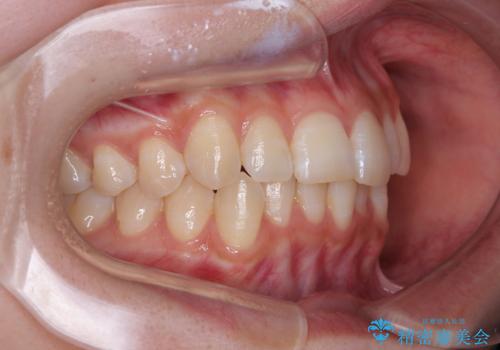

- 上下前歯の重なりを気にして来院された患者様です。

安価なインビザラインパッケージを用いての治療を希望されており、デコボコの程度が中等度であったため、インビザライン・モデレートを用いて矯正治療を行うこととしました。